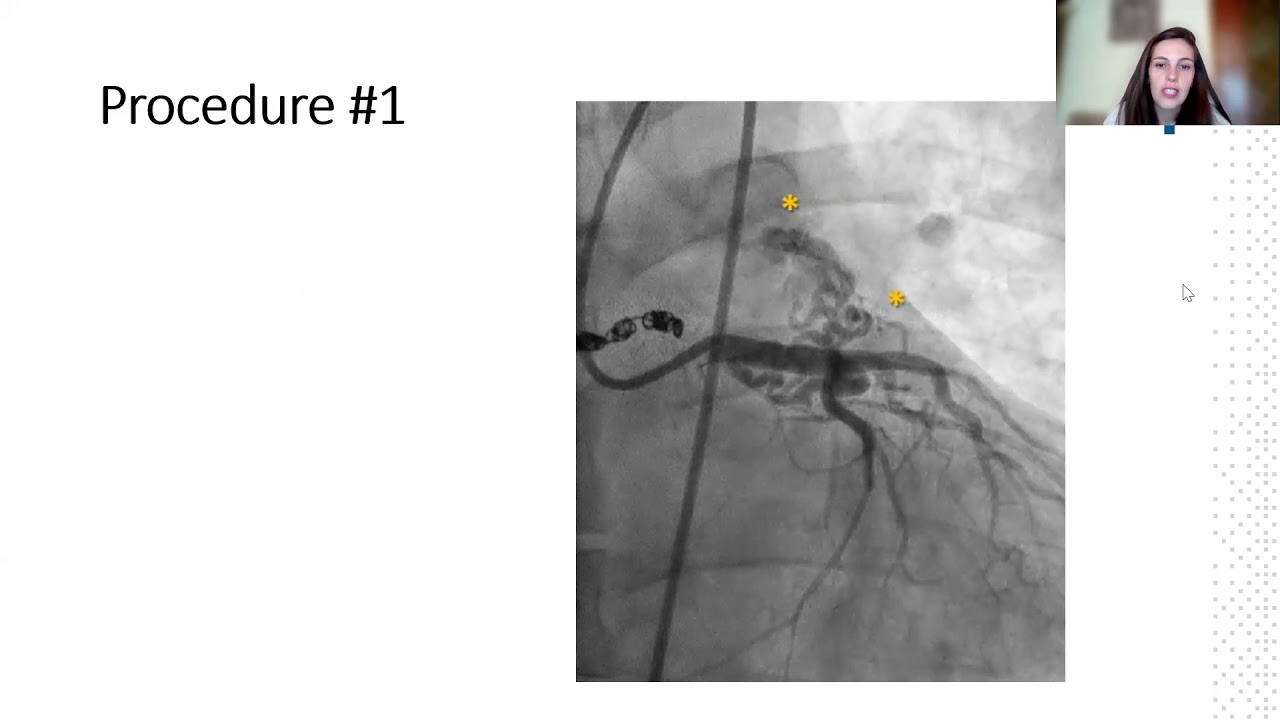

Transcatheter closure of recanalized large coronary-cameral fistula.

By: Lyubomir Dimitrov, National Heart Hospital, Sofia, Bulgaria

Multiple coronary fistulae as cause of myocardial ischemia in a patient with hypertrophic cardiomyopathy.

By: Maria Tamargo, General University Hospital Gregorio Marañon, Madrid, Spain